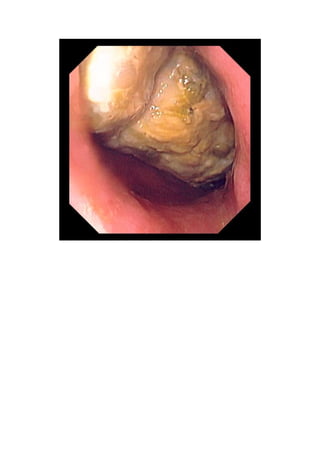

upper endoscopy is usually done. On endoscopy, bezoars have an unmistakable

irregular surface and may range in color from yellow-green to gray-black. An

endoscopic biopsy that yields hair or plant material is diagnostic.